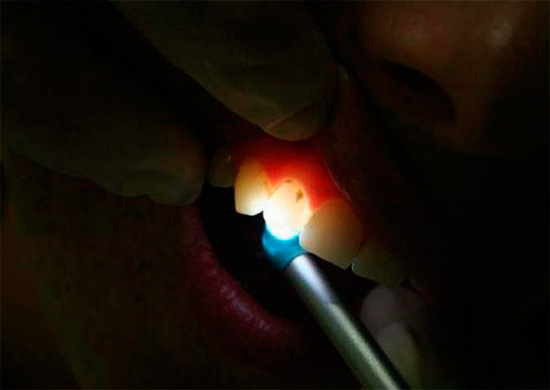

- Transillumination e diagnostica luminescente. Entrambi questi metodi rivelano nascosti danni ai denti cariati in qualsiasi momento.